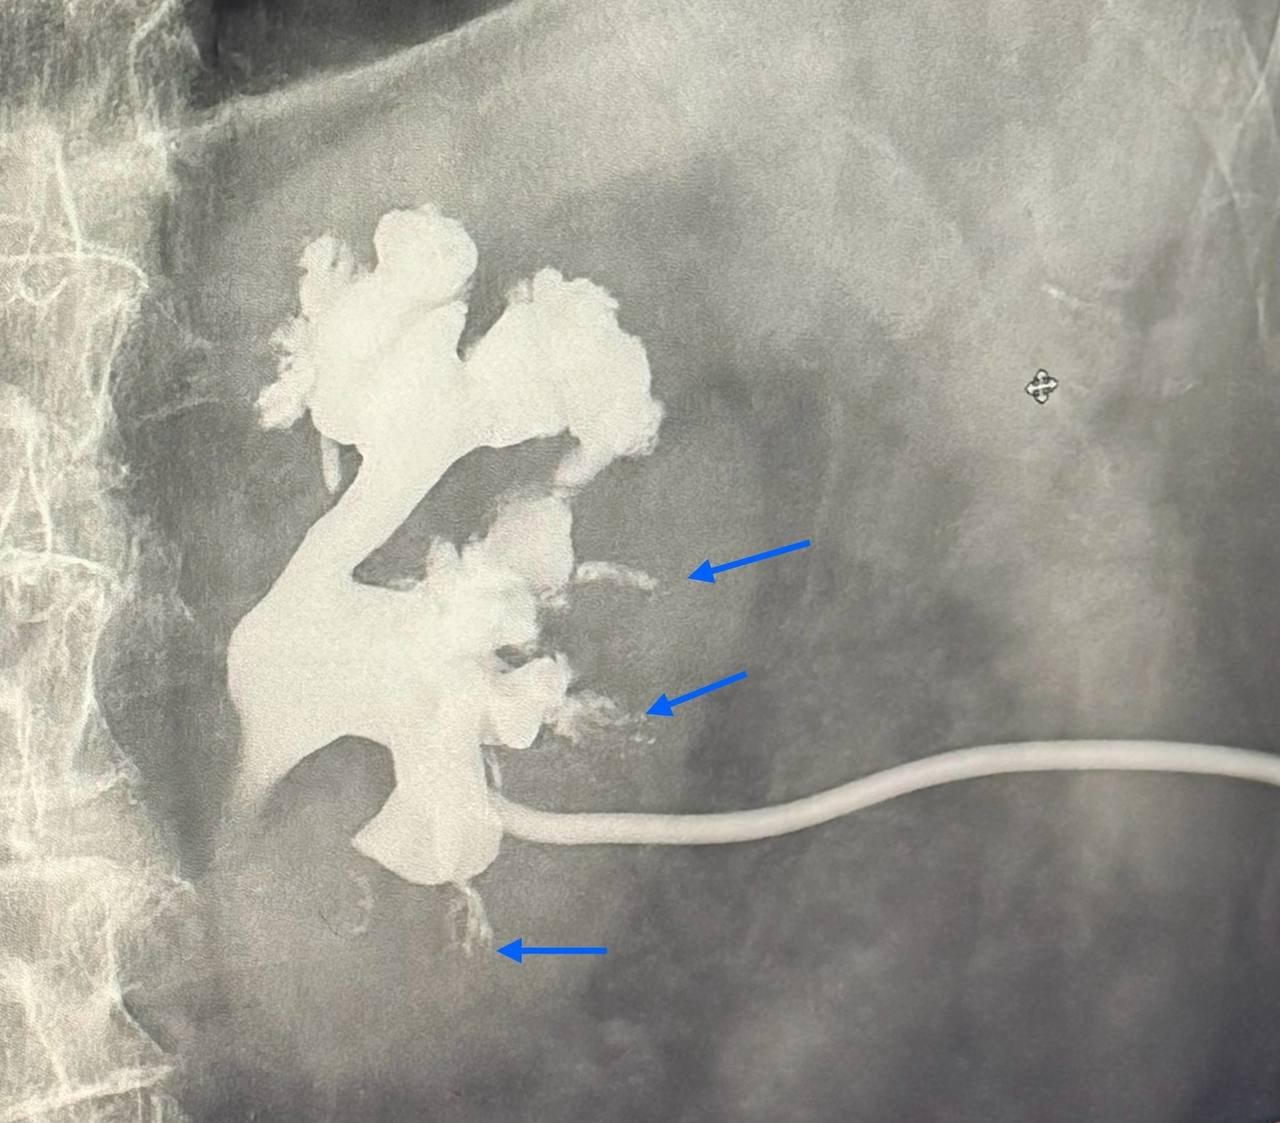

Лоханочно-почечные рефлюксы бывают форникальными (нарушение целости слизистой чашечки в области форникса) и тубулярными (проникновение содержимого лоханки в почечную ткань по собирательным канальцам).